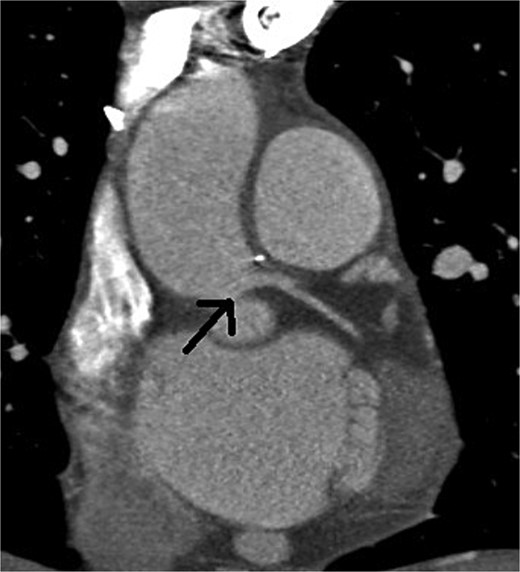

A 46-year-old female presented with recurrent chest pain radiating to the left arm accompanied by dyspnea. She was a non-smoker with no significant past medical history. Physical examination, laboratory results, chest X-ray, and electrocardiogram were all normal. Transthoracic echocardiography showed normal valvular function, a left ventricular ejection fraction of 63%, and mildly impaired diastolic function. Multislice computed tomographic coronary angiography revealed sub-total occlusion of the left main coronary artery, starting at the ostium and extending 5 mm distally (Fig. 1). Cardiac catheterization revealed a right-dominant coronary circulation, with a 90% stenosis in the ostial and proximal shaft of the left main coronary artery, with no other lesions detected (Fig. 2).

Preoperative multislice computed tomographic coronary angiography revealing sub-total occlusion of left main coronary artery, starting at the ostium and extending 5 mm distally (arrow)